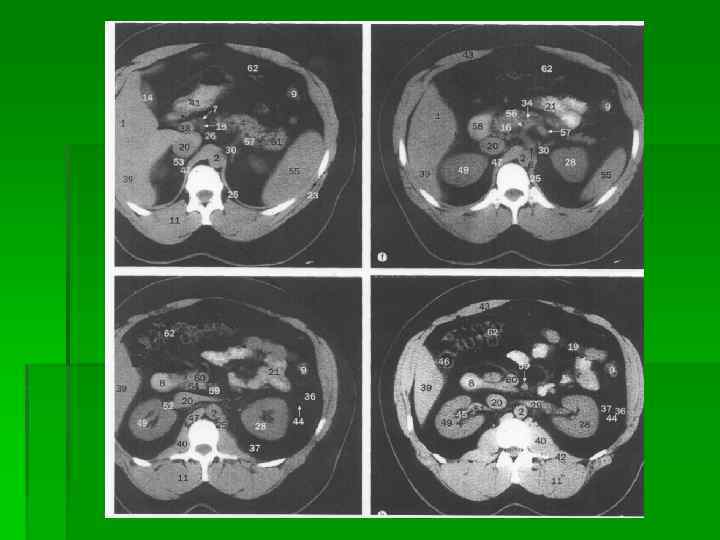

Области передней брюшной стенки человека

Скелетотопия желудка